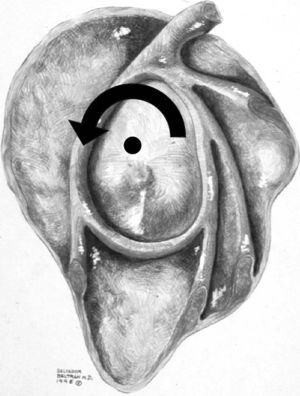

Con el brazo en abducción a 90 grados, el hombro puede realizar una rotación externa, a partir de la horizontal, de aproximadamente 100 a 120 grados, y una rotación interna de aproximadamente 100 a 120 grados, dependiendo del entrenamiento. Durante este movimiento la cabeza humeral tiene su punto de rotación en el centro de la cavidad glenoidea y el trocánter describe un arco centrado en este punto (fig. 5).

Fig. 5.--Esquema de la cavidad glenoidea y la cápsula donde se puede observar el centro de rotación normal de la cabeza humeral con el brazo en abducción (punto negro) y el arco de rotación del trocánter (flecha curva).